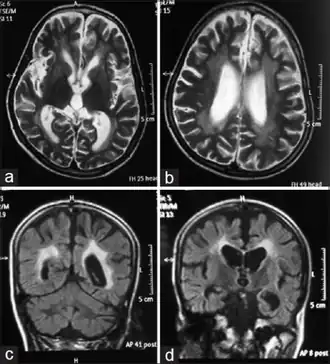

- Encephalopathy